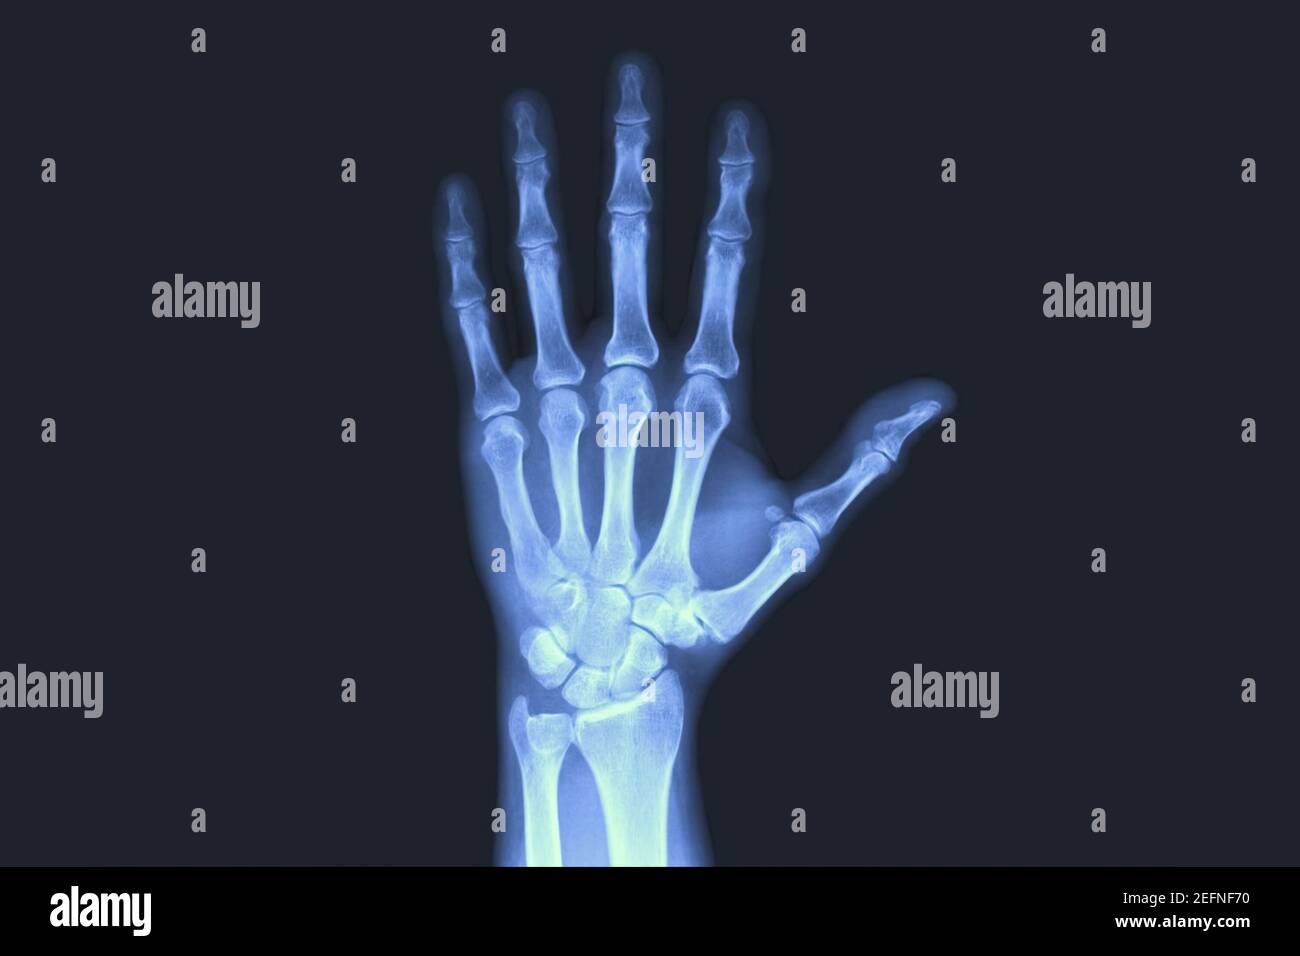

Normal hand, Xray Stock Image C039/3288 Science Photo Library

Labeled X Ray Of Hand . Web hand radiographs are commonplace in the emergency department or the trauma reporting list. Web  normal radiographic anatomy of the hand case contributed by samir benoudina diagnosis certain share add to Fractures and dislocations are usually straightforward to identify, so long as the potentially injured bone is fully visible in 2 planes. The hand comprises the metacarpal and phalangeal bones.

Fractures and dislocations are usually straightforward to identify, so long as the potentially injured bone is fully visible in 2 planes. The hand comprises the metacarpal and phalangeal bones. Web hand radiographs are commonplace in the emergency department or the trauma reporting list. Web  normal radiographic anatomy of the hand case contributed by samir benoudina diagnosis certain share add to